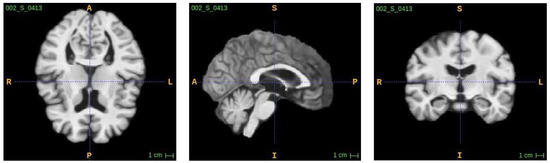

3.1. Multimodal MRI Data Collection

3.2. Image Fusing and Preprocessing